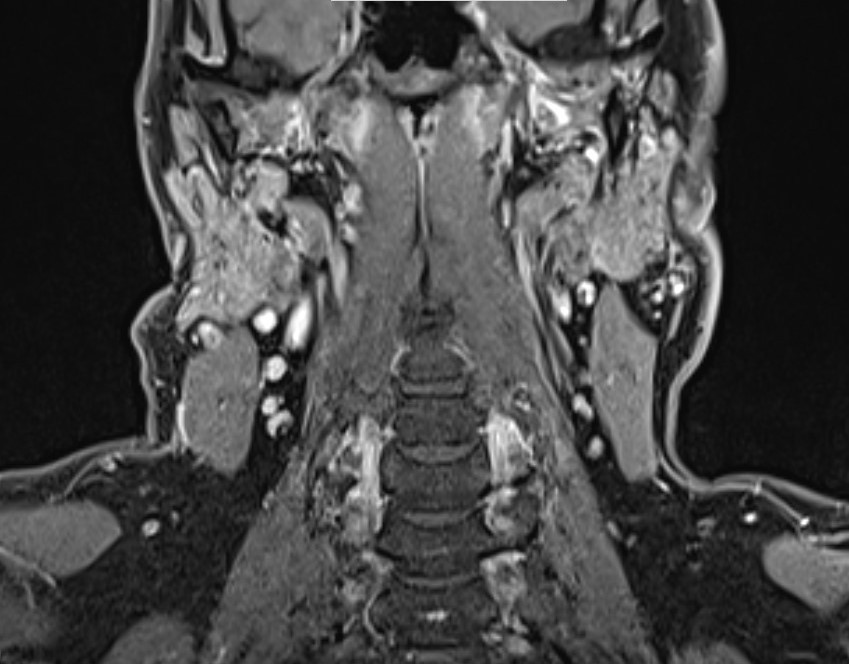

Lymphknoten in der MRT

Lymphknoten sind auf einer MRT (Magnetresonanztomographie) sichtbar, weil sie als Teil des Lymphsystems spezifische Gewebeeigenschaften besitzen, die sich von umliegenden Strukturen unterscheiden. Die MRT nutzt ein starkes Magnetfeld und Radiowellen, um detaillierte Bilder des Körpergewebes zu erzeugen. Dabei macht sich die MRT vor allem Unterschiede in der Wasserstoffkonzentration und den physikalischen Eigenschaften des Gewebes zunutze.

Lymphknoten bestehen aus lymphatischem Gewebe, das eine höhere Dichte an Zellen und Flüssigkeit aufweist als umliegende Strukturen wie Fettgewebe. Diese Unterschiede in der Gewebszusammensetzung führen dazu, dass Lymphknoten je nach verwendeter MRT-Sequenz anders erscheinen als das umliegende Gewebe. Es gibt verschiedene Sequenzen in der MRT, die unterschiedliche Gewebetypen besser hervorheben können.

Zusätzlich können veränderte oder vergrößerte Lymphknoten, die auf Infektionen, Entzündungen oder Tumore hinweisen, noch deutlicher sichtbar sein. In solchen Fällen verändern sich die Eigenschaften der Lymphknoten und sie heben sich noch stärker von gesunden Strukturen ab, was sie auf den MRT-Bildern leichter erkennbar macht.

MRT-Bilder mit Anatomie von Lymphknoten im Becken, Lymphknoten im Halsbereich, sowie einem Lymphknoten im Bereich des Schlüsselbeins: